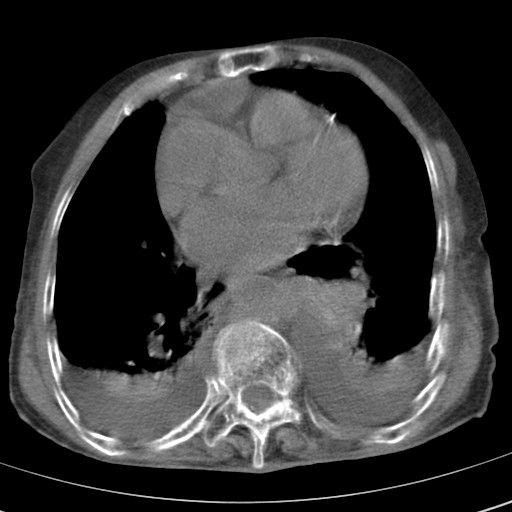

女,93岁,摔伤后检查。

右肺炎症,心功能不全伴双侧胸腔积液,右下肺膨胀不全,食管裂孔疝,冠脉钙化,心包少量积液,左侧肋骨骨折,请上传骨窗.

右侧锁骨\\肩胛骨骨折、右侧湿肺,心功能不全伴双侧胸腔积液,右下肺膨胀不全,左膈破裂或食管裂孔疝,冠脉钙化,心包少量积液,请上传骨窗.

右肺炎症,心功能不全伴双侧胸腔积液,右下肺膨胀不全,食管裂孔疝,冠脉钙化,心包少量积液,左侧肋骨骨折,右肩甲骨粉碎性骨折。93岁,高寿哇!

右肺炎症,心功能不全伴双侧胸腔积液,右下肺膨胀不全,食管裂孔疝,冠脉钙化,心包少量积液,左侧肋骨骨折,右肩甲骨粉碎性骨折。